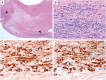

Results: Of the 160 IgG4-RD patients in this cohort, 36 (22.5%) had large-vessel involvement. The mean age at disease onset of the patients with large-vessel IgG4-RD was 54.6 years. Twenty-eight patients (78%) were male and 8 (22%) were female. Thirteen patients (36%) had primary IgG4-related vasculitis and aortitis with aneurysm formation comprised the most common manifestation. This affected 5.6% of the entire IgG4-RD cohort and was observed in the thoracic aorta in 8 patients, the abdominal aorta in 4, and both the thoracic and abdominal aorta in 3. Three of these aneurysms were complicated by aortic dissection or contained perforation. Periaortitis secondary to RPF accounted for 27 of 29 patients (93%) of secondary vascular involvement by IgG4-RD. Only 5 patients demonstrated evidence of both primary and secondary blood vessel involvement. Of those treated with rituximab, a majority responded positively.

Conclusions: IgG4-RD is a distinctive, unique, and treatable cause of large-vessel vasculitis. It can also involve blood vessels secondary to perivascular tumefactive lesions. The most common manifestation of IgG4-related vasculitis is aortitis with aneurysm formation. The most common secondary vascular manifestation is periaortitis with relative sparing of the aortic wall. Both primary vasculitis and secondary vascular involvement respond well to B cell depletion therapy.